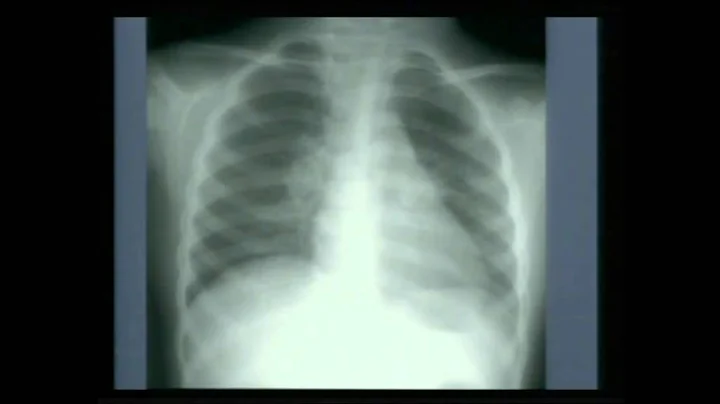

Tuberculosis Primary (part 2)